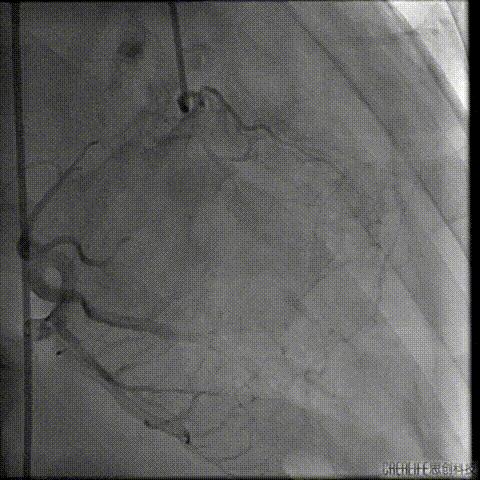

预扩主动脉瓣

NUMED 25mm*40球囊

180/分起搏下预扩主动脉瓣

左冠血流受到影响

予ECOM支持

扩瓣结束后,患者出现心跳骤停

予胸外按压,并予ECOM支持后

患者恢复自主心率